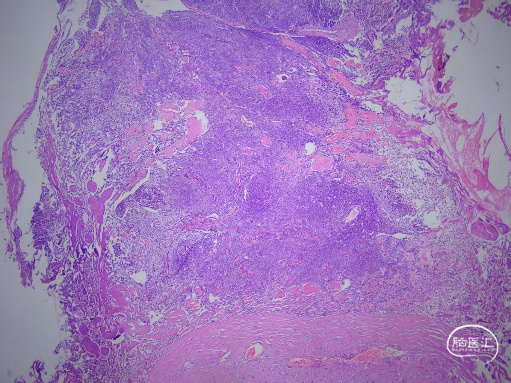

术后病理:脑膜瘤,WHO Ⅰ级。免疫组化:肿瘤细胞EMA(+),SSTR2(+),PR(+),β-catenin(膜浆+),GFAP(-),S-100(-),SOX-10(-),Desmin(-),ATAT-6(-),AE1/AE3(-),CD34(血管+),Ki-67(2%+)。